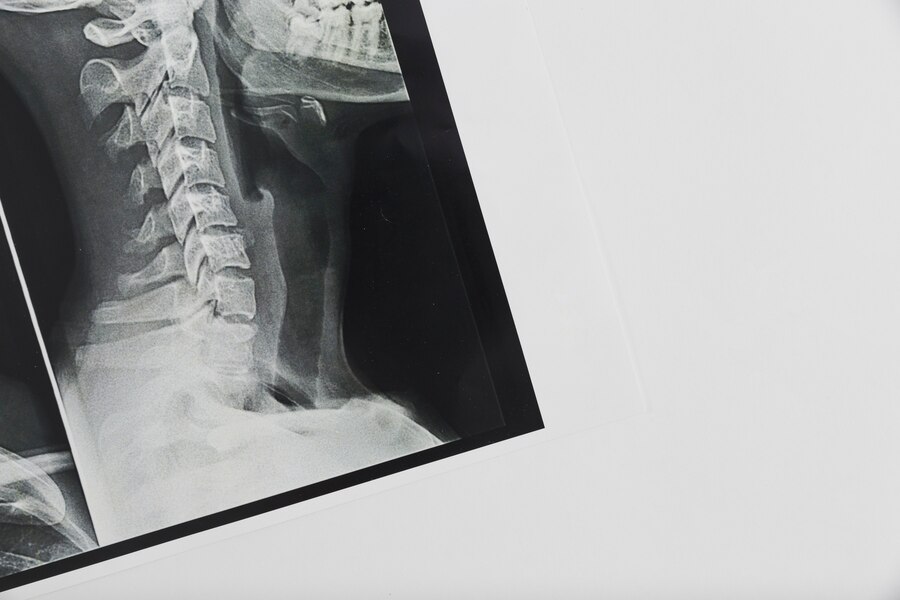

Rayos X

Es una prueba rápida e indolora que genera imágenes de las estructuras internas del cuerpo mediante dosis de radiación ionizante.

Ejemplo de Imagen informativa